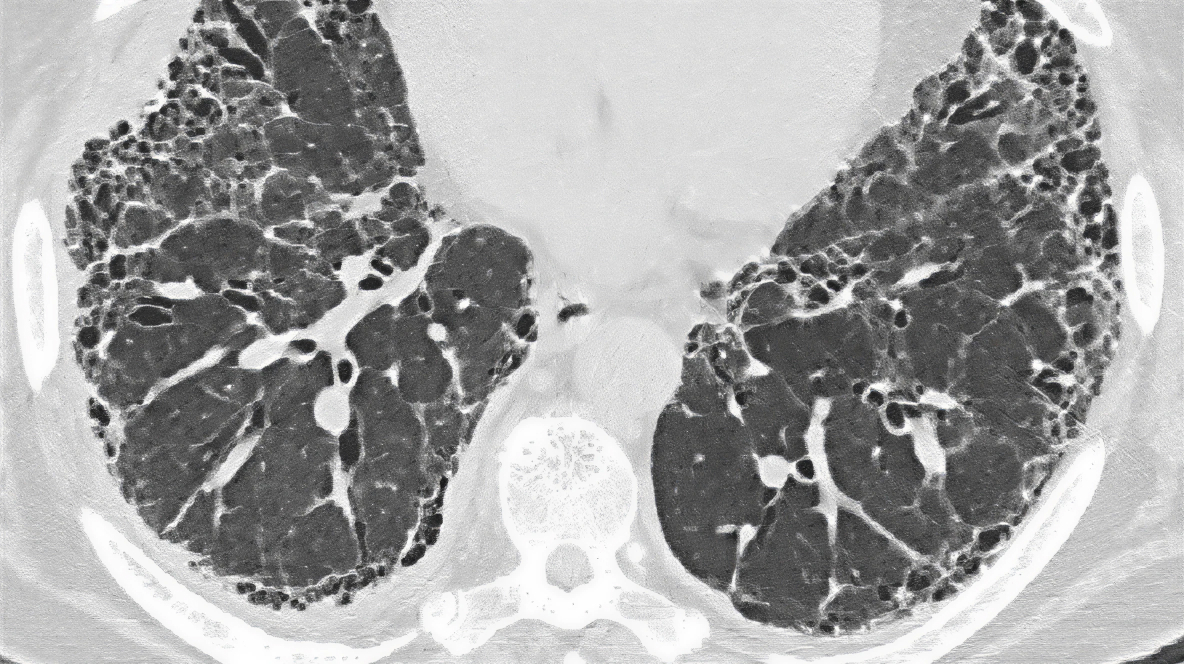

OBRAZ „PLASTRA MIODU”

Cechy

• Skupiska torbielowatych przestrzeni powietrznych o wyraźnych ścianach, o średnicy 2–10 mm, czasami dochodzącej do 25 mm, zwykle w okolicach podopłucnowych

Cechy związane z obrazem „plastra miodu”

• Wewnątrzzrazikowe zmiany siateczkowe

• Trakcyjne rozstrzenia oskrzeli i rozstrzenia oskrzelików

• Utrata objętości płata

• Zniekształcenia szczelinowe

Obraz plastra miodu

Podopłucnowe zmiany typu „plastra miodu” tworzące kilka warstw torbieli u 73‑letniego mężczyzny z UIP